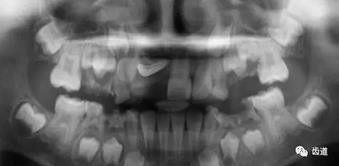

2、多生牙

多生牙的定位